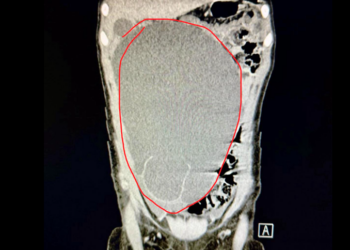

Durerile abdominale la copii sunt unul din principalele motive de prezentare la Urgențe. Mai exact, apendicitofobia îi trimite pe majoritatea la verificat. În practică, însă, 90% sunt de fapt gaze ...